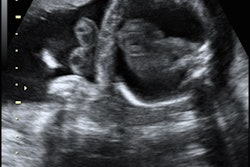

22 abril 2019 -- Historia: Un hombre de unos 70 años acude por sudoración nocturna observada en el último mes. No tiene fiebre ni antecedentes de enfermedades anteriores. En el análisis sanguíneo se observa una elevación de la velocidad de sedimentación, la proteína C reactiva y la fosfatasa alcalina.

Se deriva al paciente para la realización de una TC de tórax y abdomen. A continuación se muestran imágenes de la TC axial. Haga clic para ampliar.